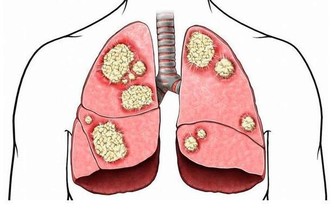

5,胸片

可以發現症狀不明顯的肺結核、肺癌。尤其是吸煙多年的人更應定期檢查,以便早期發現肺癌。